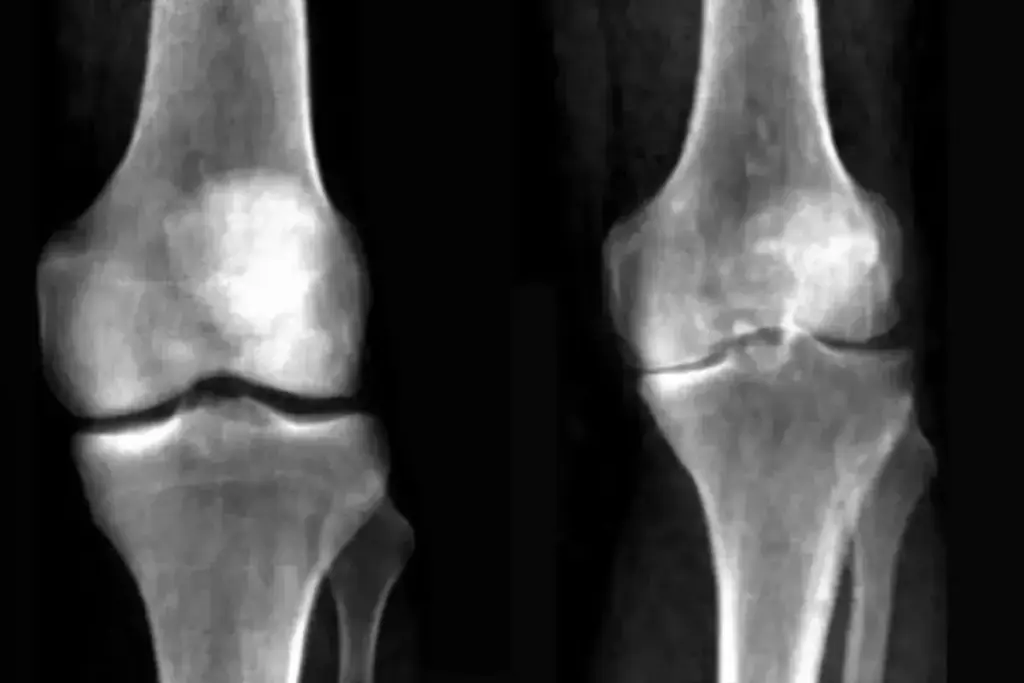

Advantages of MRI Over X-rays

MRI beats X-rays for arthritis diagnosis. MRI sees soft tissue changes, like inflammation and cartilage damage, without radiation.

- MRI finds early joint damage, leading to early treatment.

- It checks the health of bones, cartilage, and soft tissues fully.